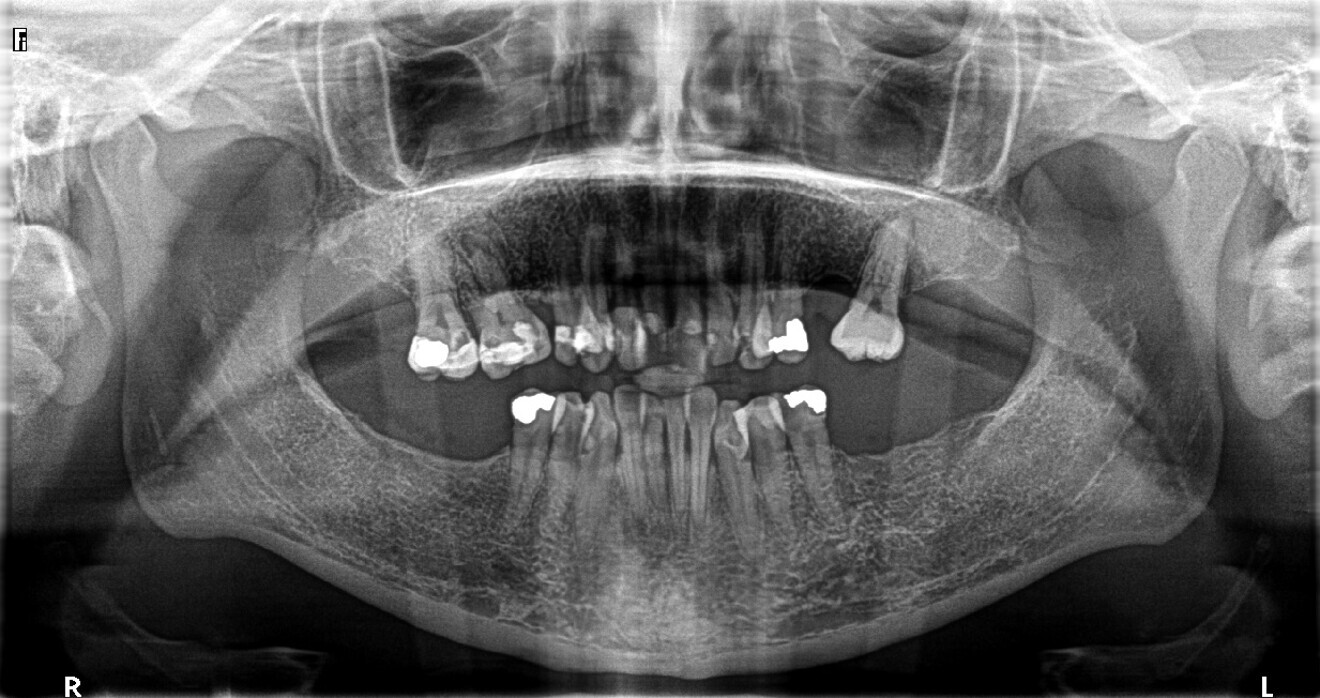

A CBCT scan and panoramic radiograph using the CS 8100 3D (Carestream Dental; Fig. 3) were taken to accurately capture the information needed to properly plan the treatment for this case that would ensure the most ideal outcome, especially since the patient had discussed how unhappy she was with her existing gummy smile. Using the CS 3D imaging software (Carestream Dental), dental implants were virtually planned in key positions to biomechanically support a full-arch fixed hybrid restoration in the maxillary arch (Fig. 4).

Fig. 3: Pre-op panoramic radiograph.